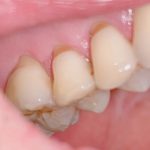

上の写真は歯の根本がけずれてしまっているお写真です。歯の表面のエナメル質が無くなり下の層の象牙質が露出してしまっています。

象牙質は神経が存在しますのでピリピリ痛いんです♪

原因は歯軋りなどある一定以上の力が加わるとこのような現象が起きます(^o^)

消毒をして人工エナメル質を接着させました。

この処置は全く痛くありません、思い当たるかたは処置を受けてみてください。☘️☘️

楽になりますし見た目も、とても綺麗ですよ💁♀️💕